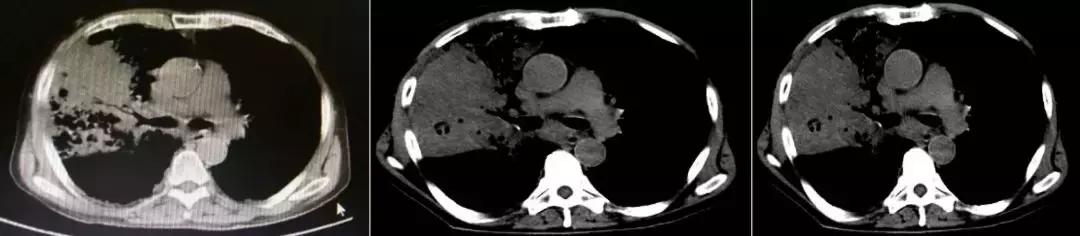

1天前急救车于我院急诊,血常规提示白细胞明显升高,胸部CT(2017-3-15):两肺感染,右肺上叶中叶膨胀不全,两肺间质改变,两肺肺气肿;急诊给予「头孢哌酮舒巴坦联合万古霉素」抗感染治疗,面罩10L/分吸氧维持血氧饱和度在85~95%之间,现为进一步诊治以「重症肺炎」收住我科。

CT:2018-3-15

2017-9-26

2017-9-29